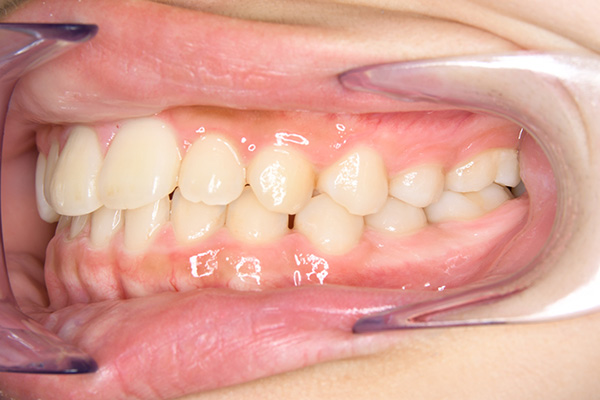

動的治療開始前(9歳7ヵ月)

動的治療開始前

(9歳7ヵ月)

口腔内所見 over jet -2.5mm、over bite 2.0mm、大臼歯関係はⅠ級 。Hellmanのdental ageはⅡCであり前歯部は反対咬合を呈していた。